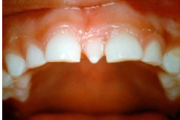

Vali sind huvitav pilt ja me näitame sellega seotud haigust ja sümptomeid